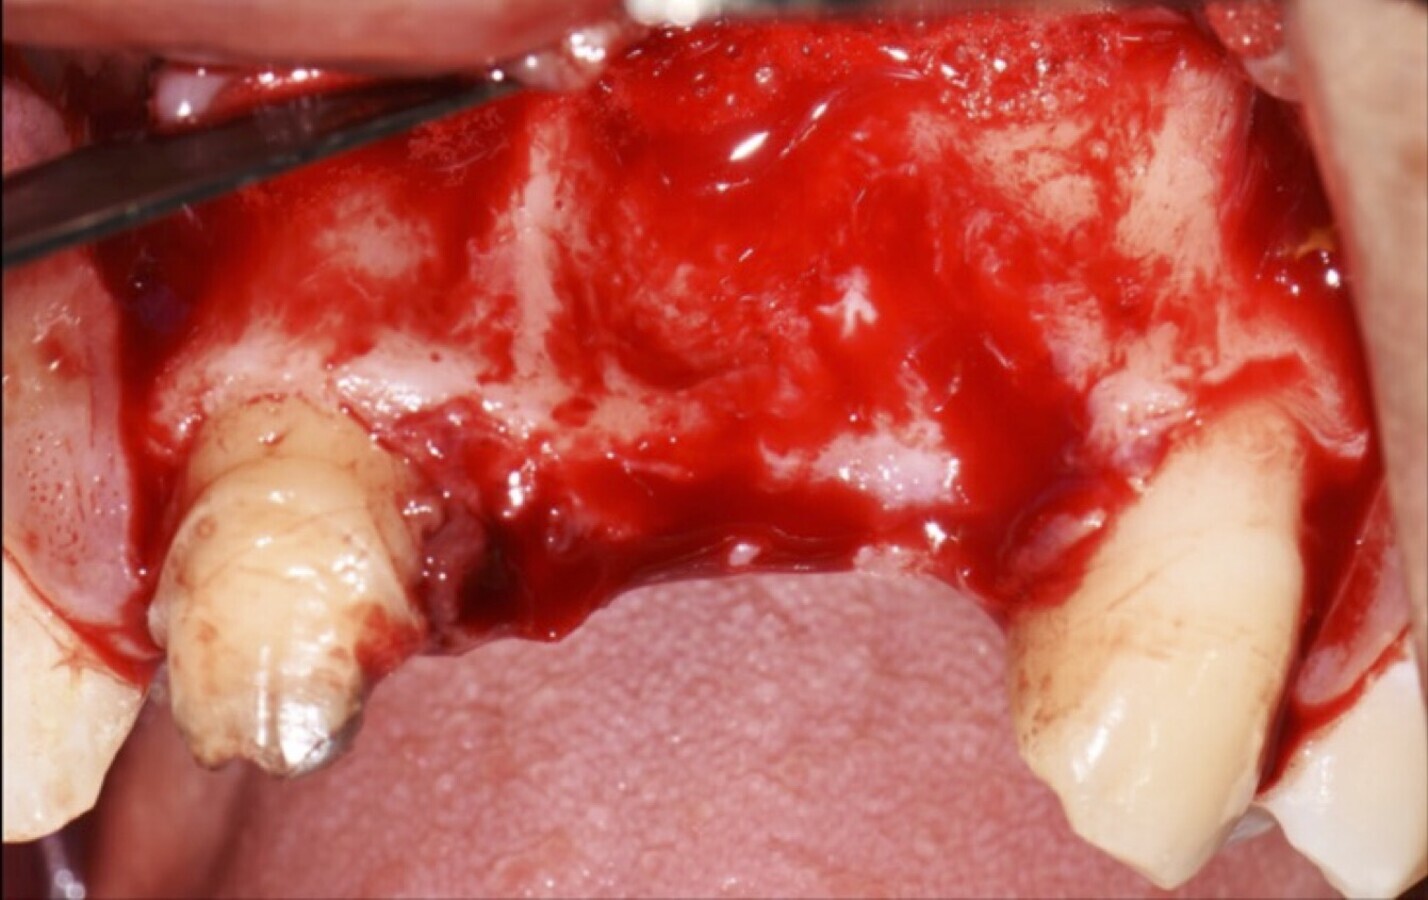

Figura 24. Imágenes de la verificación del sangrado proveniente de la zona medular (a, b).

Paciente de sexo femenino de 36 años de edad, llega a la consulta por presentar una restauración protésica inadecuada. En el examen clínico se observa una restauración protésica provisional acrílica sobre las piezas 1.1 y 2.2. Adicionalmente, se aprecia recesión gingival a nivel de la pieza 2.2 y deficiencia horizontal severa de reborde a nivel de la zona edéntula correspondiente a la pieza 2.1. En la evaluación tomográfica se observa ausencia total de tabla ósea vestibular en la pieza 2.2, y se corrobora el déficit en la zona edéntula de la pieza 2.1, para lo cual se indica una reconstrucción de estructuras óseas con hueso en bloque de origen bovino y posteriormente la colocación de implantes dentales.

Figura 36. Defecto óseo y severa reabsorción ósea horizontal: vista clínica (a) y corte tomográfico (b).

Figura 45. Afrontamiento de colgajo y sutura (a - e). Control a los 7 días postquirúrgico (f).